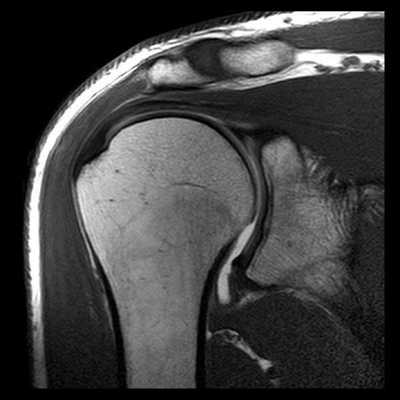

КТ плечевого сустава. Оскольчатый перелом хирургической шейки плечевой кости со смещением отломков. Дистальный отломок (красная стрелка) вколочен в проксимальный отломок (синяя стрелка).

У каждого способа обследования имеются свои преимущества и недостатки. На сегодняшний день ведущую роль в визуализации вне- и внутрисуставных структур плечевого сустава играет МРТ, которая позволяет выявлять мягкотканные и костные повреждения в суставах. Она может осуществляться по двум базовым протоколам - бесконтрастная томография и МРТ плечевого сустава с применением парамагнитных контрастных веществ (она же МР артрография). Лидирующую роль в оценке состояния костей плеча играет спиральная компьютерная томография.